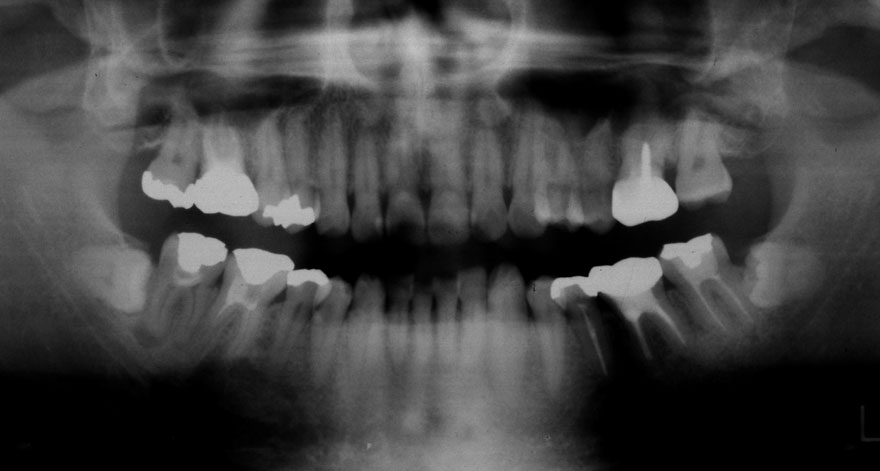

開始年齢 20代

初診時 24歳 女性

19年後 43歳

初診時 24歳 女性 平均歯槽骨喪失量:1.57mm

平均歯槽骨喪失量:1.72mm

22年間喪失量:-0.15mm

年間喪失速度:-0.007mm

(ケア頻度:1.35ヵ月ごと)